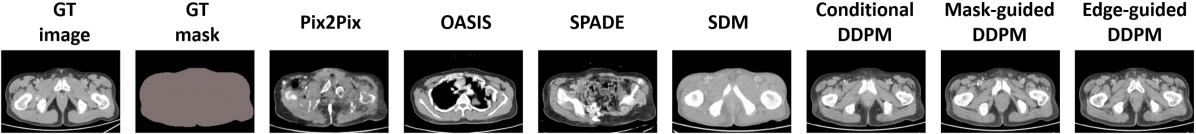

Comparison study. We carried out a quantitative evaluation of the diffusion models against other SOTA algorithms such as Pix2Pix, OASIS, SPADE, and SDM methods. In terms of image quality metrics such as FID, PSNR, and SSIM, the diffusion models outperformed non-diffusion-based methods. However, in terms of learned correspondence metrics like DSC, diffusion models surpassed other models for larger organs such as the liver, spleen, and kidneys. The OASIS method achieved superior performance for relatively small organs and structures like gallbladder and left adrenal gland. This may be because OASIS was good at synthesizing the clear boundary between small organs and the background, resulting in better segmentation results by TS and thus having higher DSC scores. Fig. 4 presents multiple results ranging from the lower to the upper abdomen, from different methods. It is worth noting that from the top row of Fig. 4 GAN-based methods struggled to synthesize images when the number of mask classes was sparse. For example, Pix2Pix and SPADE were unable to generate realistic images. OASIS generated an image from the upper abdomen, which was inconsistent with the location of the given mask. The bottom row illustrated the same trend. GAN-based models failed to synthesize the context information within the body mask, for example, the heart and lung. On the contrary, diffusion models including the SDM model succeed to generate reasonable images based on the given masks. One explanation was that diffusion models were more effective when the number of masks decreased and the corresponding supervision became sparser.

Figure 4: Results from different semantic image synthesis methods. The color map for different organs: body (beige), spleen (green), liver (dark red), right kidney (blue), left kidney (yellow), stomach (indigo), aorta (light brown), duodenum (light purple), pancreas (gray), right/left adrenal gland (dark/light green), inferior vena cava (aqua blue green), bladder (shallow brown), prostate (purple).